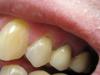

bojun Опубликовано 26 октября, 2007 Поделиться Опубликовано 26 октября, 2007 Зашла к врачу (думала, что это - парадонтит) - "успокоил": "нет, только дефект эмали, надо пломбировать, но можо и так ходить..." Никакой там реминирализующей терапии, никаких рекоммендаций, конкретных диагнозов... (клиновидный? эрозия?... еще что? ) Скажите, пожалуйста, что это у меня? на какой стадии? что делать? - реминирализация или уже пломбировать?а пломбы при таких делах обыкновенные? а это дело под пломбой дальше расти не будет? я вот боюсь - как же мне будут это дело "сверлить" - еще больше эмаль повредят?... И что, кислого ничего не есть? лимоны, гранаты, сухое вино - забыть, да? или если сразу полоскать, то можно? Спасибо, что есть такой ваш форум, где, надеюсь, получу квалифицированный ответ и совет! Ссылка на комментарий

Снежана Опубликовано 27 октября, 2007 Поделиться Опубликовано 27 октября, 2007 Зашла к врачу (думала, что это - парадонтит) - "успокоил": "нет, только дефект эмали, надо пломбировать, но можо и так ходить..." Никакой там реминирализующей терапии, никаких рекоммендаций, конкретных диагнозов... (клиновидный? эрозия?... еще что? ) Скажите, пожалуйста, что это у меня? на какой стадии? что делать? - реминирализация или уже пломбировать? а пломбы при таких делах обыкновенные? а это дело под пломбой дальше расти не будет? я вот боюсь - как же мне будут это дело "сверлить" - еще больше эмаль повредят?... И что, кислого ничего не есть? лимоны, гранаты, сухое вино - забыть, да? или если сразу полоскать, то можно? Спасибо, что есть такой ваш форум, где, надеюсь, получу квалифицированный ответ и совет! Это у вас клиновидные дефекты, лучше их запломбировать, т.к. эмаль в области дефектов уже стерлась и дырочки будут постепенно увеличиваться. Пользуйтесь мягкой зубной щеткой и пастой для зубов с повышенной чувствительностью, при чистке зубов исключите горизонтальные движения зубной щеткой. От лимонов лучше отказаться. Пломбы при любых делах лучше качественные светоотверждаемые. Ссылка на комментарий

NataLee Опубликовано 27 октября, 2007 Поделиться Опубликовано 27 октября, 2007 (изменено) Док, просьба перенести тему в "наш" раздел, дабы мы могли пообщаться с доктором. А то здесь как-то не комфортно Пока тема ещё здесь... парочку слов скажу. Надо найти причину этих клиновидных дефектов. А причина в данном случае, как мне представляется - неправильный прикус. Прежде чем что-то делать, нужна консультация ортодонта (и в оптимале - исправление прикуса). Иначе и пломбирование, и пасты бесполезны. После получения резюме ортодонта, если дело всё-таки в прикусе - пломбирование дефектов и ортодонтическое лечение. Касательно использования пасты для снижения чувствительности: на семинаре компании "GlaxoSmithKline" (Сенсодин) нам давали такую схему: 1 неделю - ежедневно, далее 2-3 раза в неделю. Изменено 27 октября, 2007 пользователем NataLee Ссылка на комментарий

Мартовский Опубликовано 27 октября, 2007 Поделиться Опубликовано 27 октября, 2007 В общем смысл ответа такой - не только ваш врач затрудняется с постановкой точного диагноза. Если это эрозия, то реставрация даст нужный эффект. Если клиновидный дефект, то эффект будет временный, нужно искать причину его возникновения, а она в перегрузке зубов, которая может возникнуть из-за прикуса, заболеваний парадонта. Коллеги, я все правильно перечислил? Ссылка на комментарий

bojun Опубликовано 28 октября, 2007 Автор Поделиться Опубликовано 28 октября, 2007 большое спасибо всем! начала пользоваться пастой biocalcium (с гидроксиапатитом, натуральным биоактивным кальциеми бикарбонатом натрия) и Лакалют... и еще полоскатель с фтором , мелиссой, ромашкой и шалфеем... правильно? (правда, купила все это до тоого, как прочитала ваши рекоммендации. ) пойду схожу к другому врачу завтра... Начет причин моего КД скажу вот что:- во-первых, еще в детстве говорили, что прикус у меня не правильный (верхняя челюсть слегка вперед), но отклонение маленькое, видимо, поэтому с ним не боролись... Это что, сейчас брэкеты надевать, да? лучше бы в детстве поносила... - у меня в последние пару лет напряженный период в жизни... в карьере... сплю плохо, просыпаюсь - челюсти болят - зубы даже во сне сжимаю... муж говорит, даже скрежещу иногда. Может, в этом и причина? Но почему тогда дефект у десны? - пардон за глупый вопрос - а не на верхней поверхности зуба? Прикус у меня не до такой степени неправильный, чтобы верхние зубы доставали до основания нижних!...Еще раз спасибо всем! И где же вы водитесь, врачи, любящие свою работу?... Только в Росии, что ли?... Ссылка на комментарий

Штаматолог Опубликовано 28 октября, 2007 Поделиться Опубликовано 28 октября, 2007 большое спасибо всем! начала пользоваться пастой biocalcium (с гидроксиапатитом, натуральным биоактивным кальциеми бикарбонатом натрия) и Лакалют... и еще полоскатель с фтором , мелиссой, ромашкой и шалфеем... правильно? (правда, купила все это до тоого, как прочитала ваши рекоммендации. ) пойду схожу к другому врачу завтра... Начет причин моего КД скажу вот что: - во-первых, еще в детстве говорили, что прикус у меня не правильный (верхняя челюсть слегка вперед), но отклонение маленькое, видимо, поэтому с ним не боролись... Это что, сейчас брэкеты надевать, да? лучше бы в детстве поносила... - у меня в последние пару лет напряженный период в жизни... в карьере... сплю плохо, просыпаюсь - челюсти болят - зубы даже во сне сжимаю... муж говорит, даже скрежещу иногда. Может, в этом и причина? Но почему тогда дефект у десны? - пардон за глупый вопрос - а не на верхней поверхности зуба? Прикус у меня не до такой степени неправильный, чтобы верхние зубы доставали до основания нижних!... Еще раз спасибо всем! И где же вы водитесь, врачи, любящие свою работу?... Только в Росии, что ли?... Если у Вас неправильный прикус и бруксизм - Вам прямая дорога к ортодонту, иначе пломбирование ничего не даст - через некоторое время все повываливается. Исправлять прикус и каппу на ночь. Ссылка на комментарий

Снежана Опубликовано 28 октября, 2007 Поделиться Опубликовано 28 октября, 2007 Этиология клиновидных дефектов до конца не изучена, есть механическая теория возникновения кл. дефектов и эрозии эмали, а так-же в возникновении эрозий может играть роль гиперфункция щитовидной железы (есть смысл сдать анализы на гормоны). Дефекты тв. тканей при эрозии симметричны (т.е. с 2-х сторон), при клиновидном дефекте чаще либо поражена одна сторона (у правшей левая), либо с одной стороны дефекты более выражены, чем с другой. Ссылка на комментарий